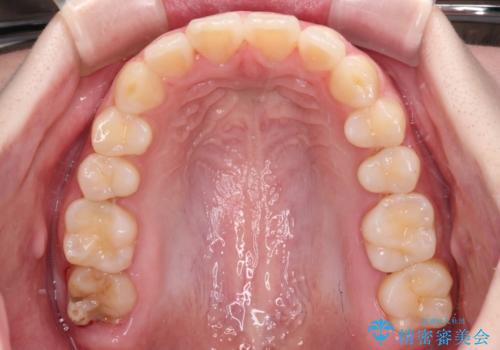

前歯のデコボコをインビザラインできれいに整える

- 前歯のデコボコと上下の隙間を気にして来院された患者様です。

前歯の捻れを改善するとともに、口元が少しでも引っ込むように治療計画を立て、仕上げることができました。